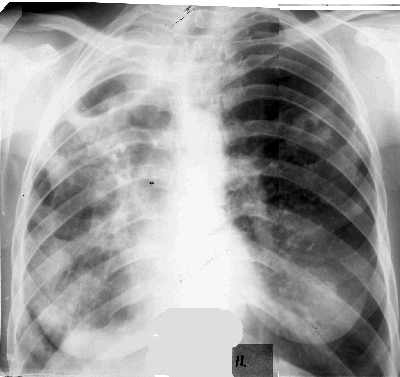

Destruktiw inçekesel görnüşleri. sirrotiki inçekesel

33

1